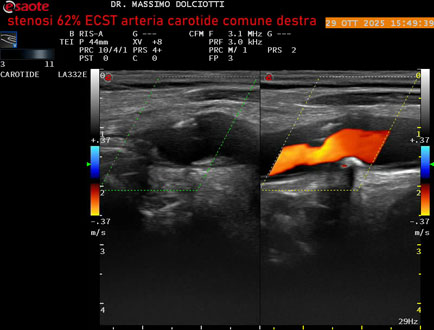

Data inserimento: 30/10/2025

Ecografia del: 29/10/2025

Strumento: Esaote MyLab Eight

Sonda: Lineare Multifrequenza 3-11 MHz

Età Paziente: F 75 anni

Motivazione dell'esame: controllo in pz con ateromasia carotidea ed ipercolesterolemia.

Commento all'esame: le immagini ed il video documentano all'arteria carotide comune destra placca disomogenea tipo 3 della classificazione di Gray Weale, che determina stenosi del 62% calcolato con metodo ECST.

Conclusioni: stenosi del 62% ECST dell'arteria carotide comune destra (62% ECST stenosis of the right common carotid artery).

Presentazione: Dr. Massimo Dolciotti - Ancona

Elaborazione digitale: Andrea Dini - Ancona